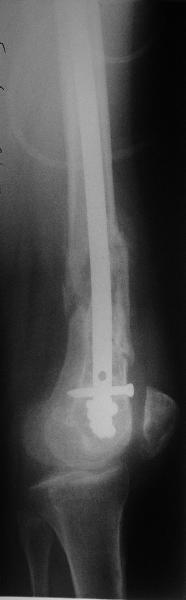

По прямой проекции неплохо. Что за стержень?

Антеградный остеосинтез при дистальных переломах бедра мы применяем давно, этот материал обобщен в канд. диссертации Александра Виноградского.

Предприятие ЦИТО выпускает доработанные нами гвозди, которые хорошо годятся для дистальных переломов, да и недороги. Можно вводть в дистальное овальное отверстие 3 винта, которые заклинивают друг друга.

Большеберцовые стержни отлично выполняют роль ретроградных бедренных. Конечно, которые не 9, а 12 мм в диаметре.

Примеры приложены.